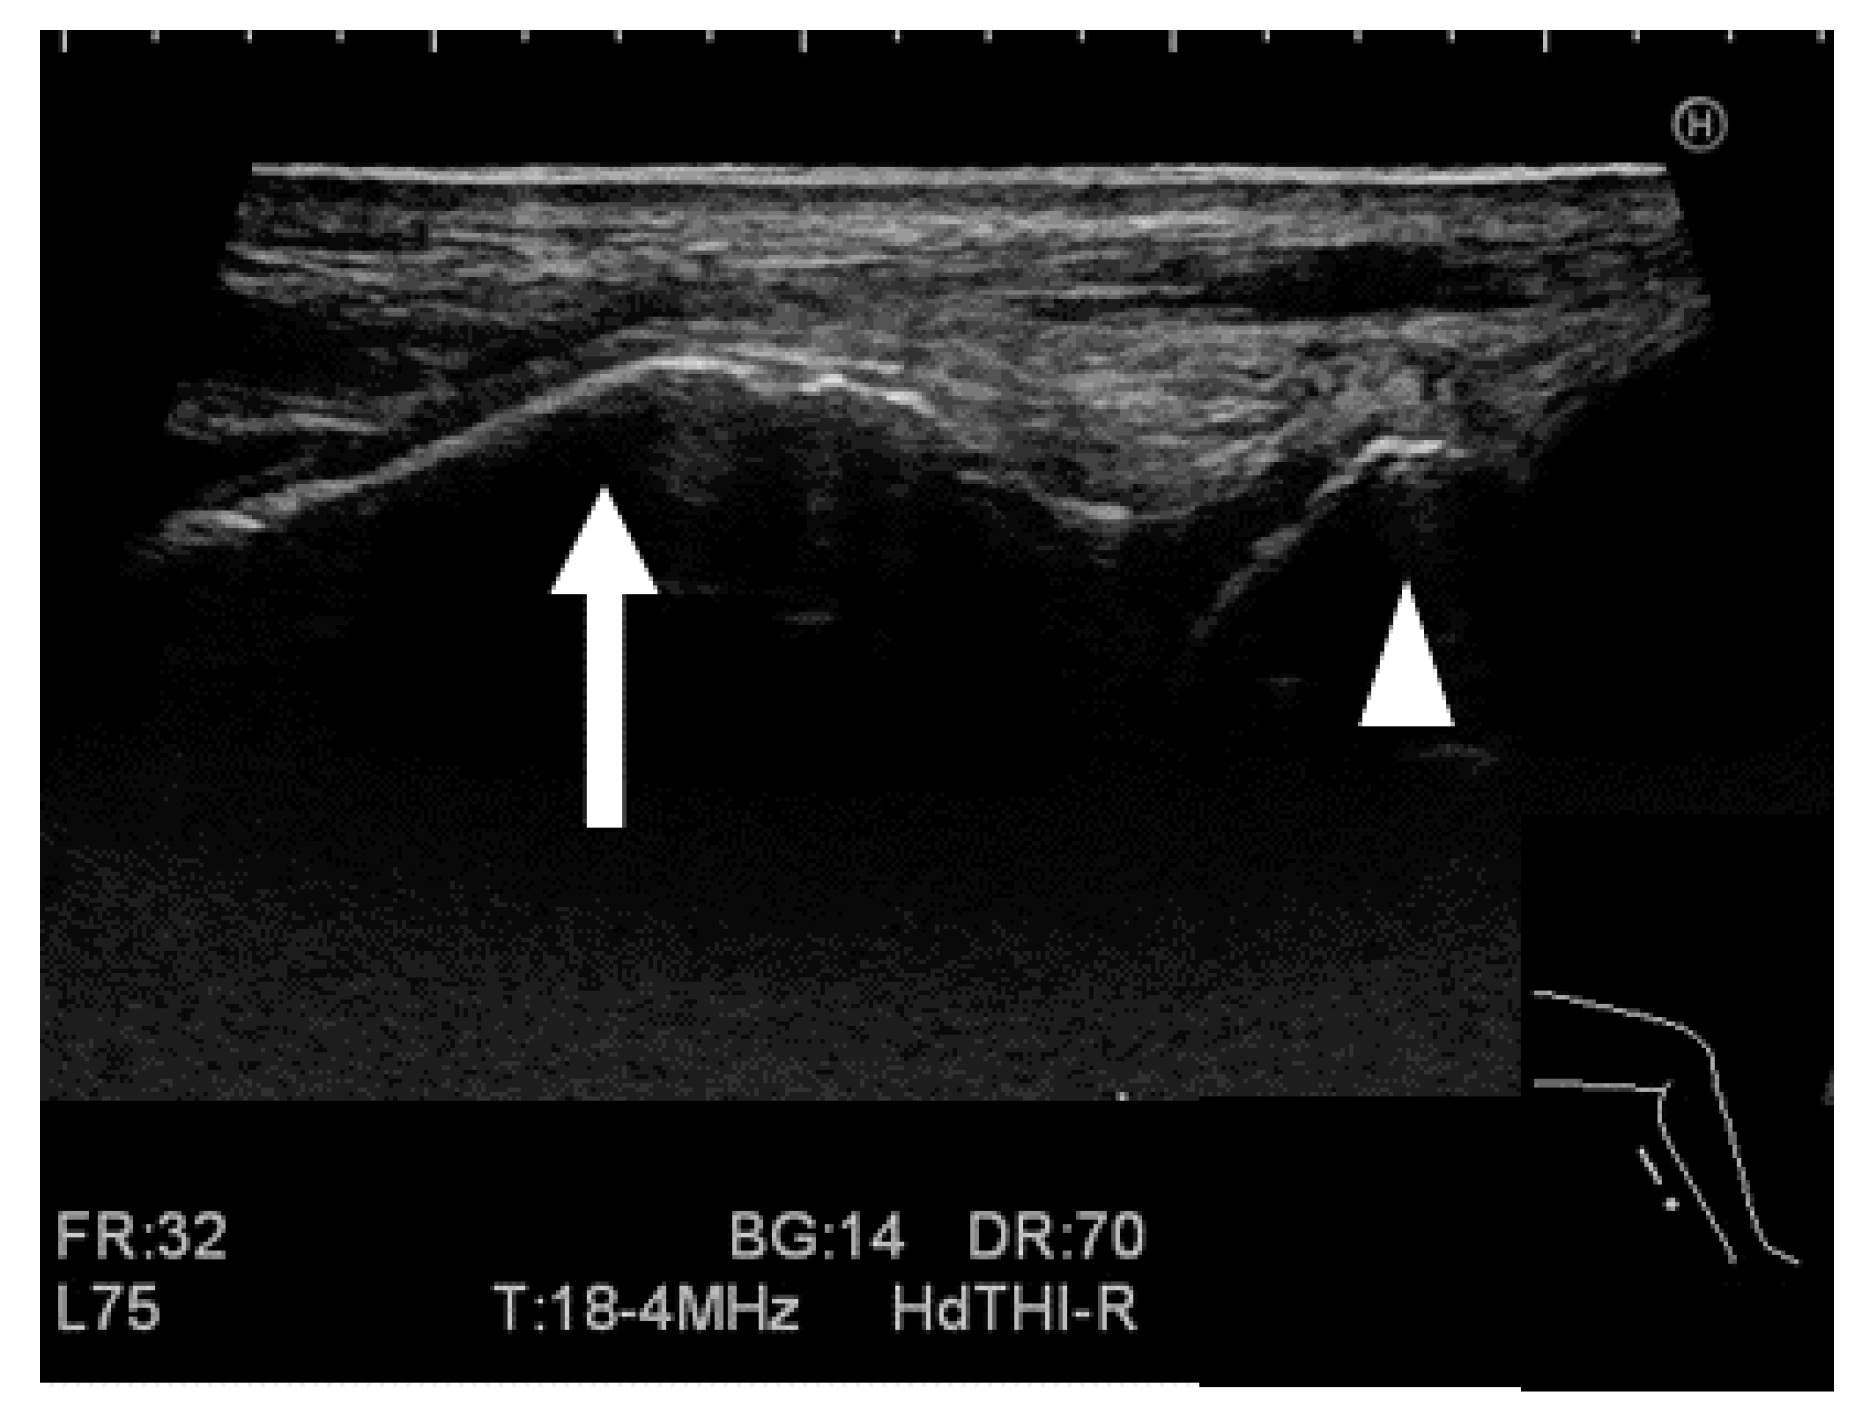

2.2.3. Ultrasound Stress Imaging Test

2.2.5. Measurement for the Stress Imaging Test